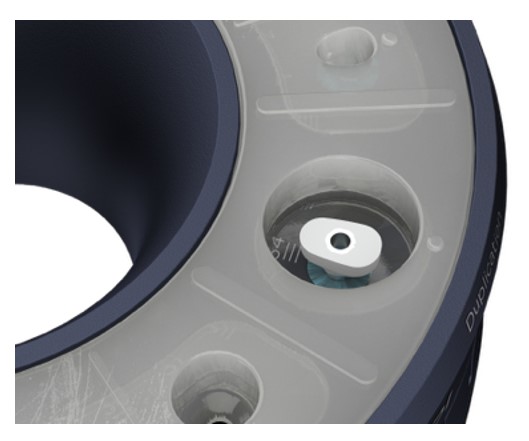

Matrița sistemului (Cervico Mold) este utilizată pentru fabricarea bonturilor de vindecare Cervico și a posturilor de amprentă (seamănă cu profilul cervical al protezei implantare dorite). Toate părțile funcționale ale matriței (bază, inserție din silicon) pot fi refolosite după o dezinfecție adecvată și un proces de sterilizare, urmând aceleași standarde ca și în cazul procesului de sterilizare a instrumentelor dentare refolosibile.

Rotește inelul superior al matriței până când forma/ dimensiunea dorită a puțului de silicon este aliniată la inserția protetică VPI dorită, prezentă în baza matriței.

Poziția fiecărei inserții de conexiune protetică VPI în interiorul bazei matriței ar trebui să fie disponibilă pe fișa informativă care însoțește kitul matriței. Acest lucru va facilita procesul de identificare a poziției inserțiilor de conectare de tip implant pentru asistent.

Rotește inelul superior al matriței până când puțul de dublare este aliniat la insertul de conexiune protetică VPI dorit prezent la baza matriței.